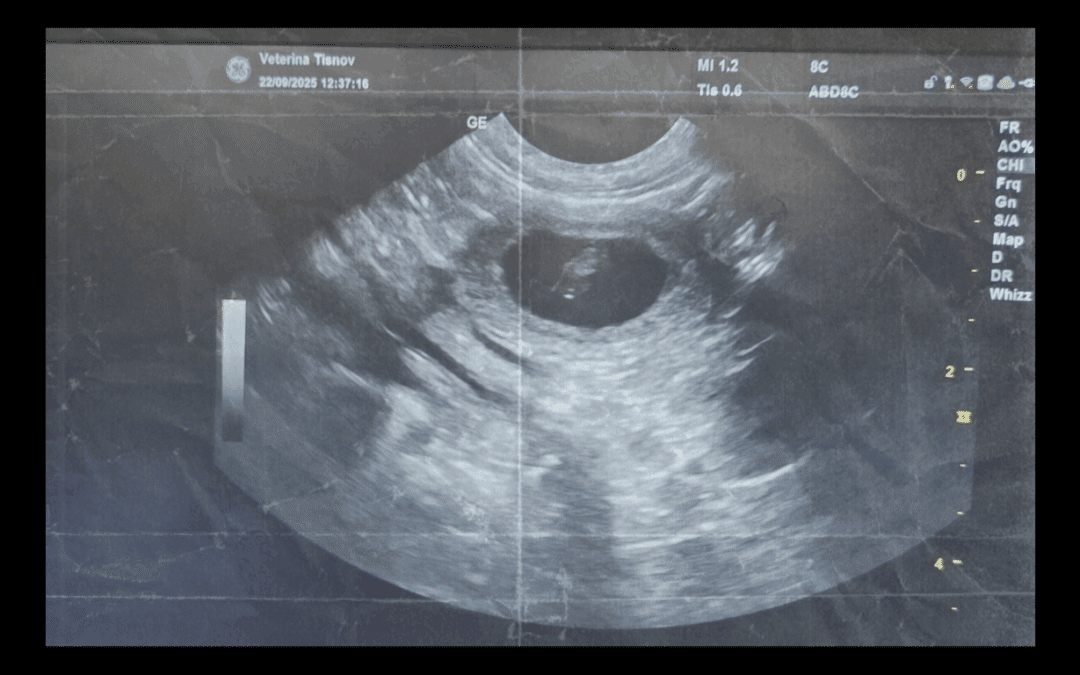

Šteniatka border kólie už túto jeseň 2025. Áno, je to tak. Sono dopadlo úspešne a ukázalo nám to, čo sme už všetci aj tak tušili. Maisynka je tehotná a krytie so Solom na konci augusta sa vydarilo. Na konci októbra/začiatkom novembra sa môžeme tešiť na malé guličky.

Maisynka sa má k svetu a tehotenstvo je na nej už vidieť.